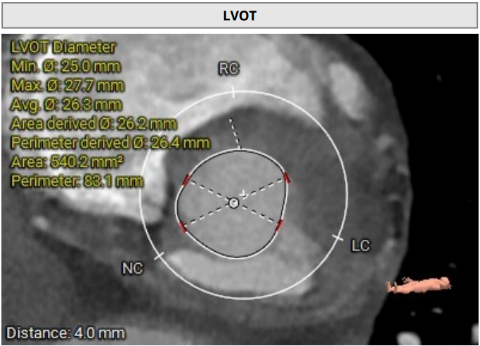

术前影像学评估 (3mensio)

瓣环及其他基本平面测量

通过术前测量,对病例深入分析,结合人工智能术前分析辅助决策软件进行三维和二维图像融合,郭应强教授指出本例手术存在以下难点:

• 左冠高度8.3mm,左窦瓣叶长度10.2mm,瓣叶明显增厚,应注意术中冠脉闭塞风险。

• 心室隔膜部长度3.3mm,新发的房室传导阻滞风险较高。

• 瓣叶钙化分布不均匀,右冠及无冠瓣叶可见明显钙化,瓣膜释放过程中存在移位风险。